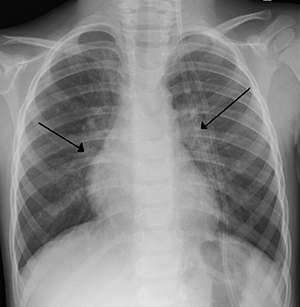

lung issuesAs of November 5, 2019, the CDC reports 2,051 cases of e-cigarette, or vaping, product use associated lung injury from 49 states (all except Alaska), the District of Columbia, and 1 U.S. territory. In addition 39 deaths have been confirmed in 24 states and the District of Columbia.

The City of Milwaukee is also sounding the alarm as there have been 16 confirmed cases of lung disease linked to ESD’s with another 15 cases under investigation. They urge people to contact their doctor if they are experiencing symptoms like nausea, chest pain, fatigue and shortness of breath.